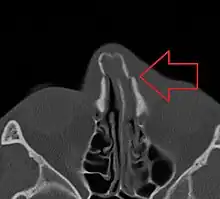

Bilateral nasal fracture as seen on CT scan